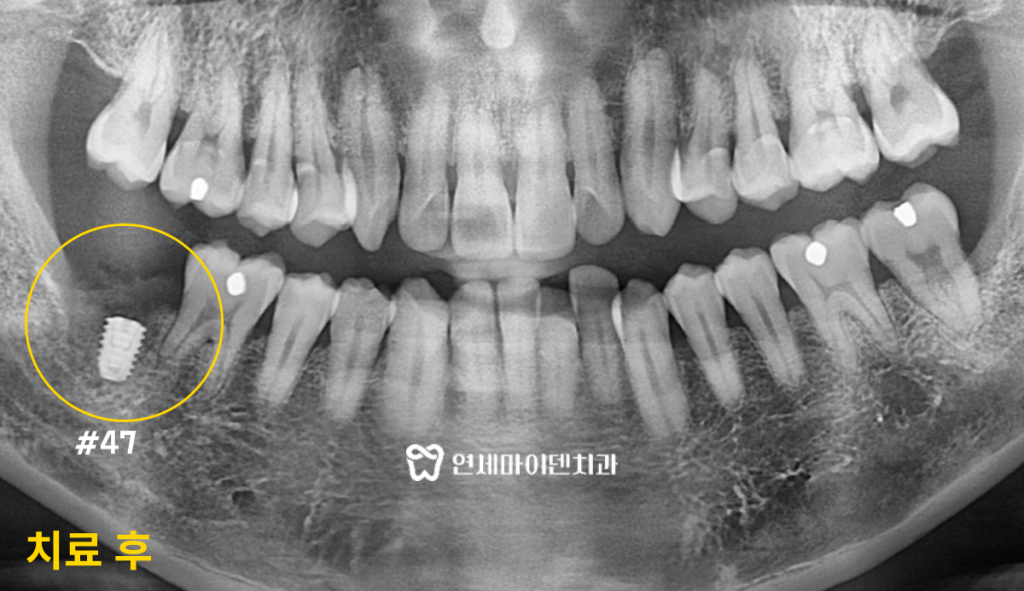

발치 즉시 임플란트 증례: 4개월 완성

안녕하세요, 소중한 치아를 지키는

연세마이덴치과 닥터꼬집 입니다.여러분, 스케일링 주기적으로 하고 계신가요?

요즘은 1년에 한 번 건강보험 적용이 되기 때문에

주기적으로 스케일링 관리를 해주시는 분이 많으십니다.하지만, 정기적인 스케일링에도 치과 치료가 필요해질 때도 있습니다.

오늘 소개해드릴 치료 사례는 주기적으로 스케일링을 받았음에도

잇몸 염증때문에 발치까지 하게 된 케이스입니다.겉으론 멀쩡해보여도 안심하면 안되는 이유

이 환자분은 오른쪽 아래 어금니가 불편해서 오셨습니다.

식사를 할 때마다 은근한 통증이 느껴지고 시큰거리는 느낌이 있다고 하셨습니다.

저희 치과에 오시기 전 다른 치과에 방문하셨지만,

발치 후 임플란트를 해야한다는 진단을 받으셨습니다.주기적으로 스케일링도 받으셨던 환자분은

치아를 살릴 수 있는 방법이 있는지 확인하시려고

<내치아 지키기 프로젝트>를 하는 저희 연세마이덴치과에 찾아오셨습니다.

씹을 때 느껴지는 통증 말고는

겉으로 보기에는 멀쩡해보이는 치아였습니다.잇몸이 살짝 붓기는 했지만, 큰 이상은 없어 보였습니다.

육안으로는 문제가 없지만 내부에 어떤 문제가 있는지

정밀 검사를 진행해보았습니다.

이 환자분의 엑스레이를 살펴보면

치아 뿌리를 둘러싼 뼈가 까맣게 녹아버린 것을 확인할 수 있습니다.받쳐주는 뼈가 없으니 치아가 흔들리고

염증은 점점 퍼지고 있는 상황이었습니다.겉으로 보기에는 멀쩡했지만,

내부는 염증으로 뼈가 녹고 있었습니다.환자분은 정기적으로 치과에 방문하셔서 스케일링을 받으셨기 때문에

갑자기 뼈가 녹았다는걸 믿지 못하셨습니다.하지만, 스케일링만으로는 잇몸 아래 깊숙히 자리잡고 있는

세균막을 제거할 수 없습니다.이 환자분은 양치질도 열심히 하시고 스케일링도 하셨지만

잇몸 아래의 세균막 관리를 하지 않아 결국 발치까지 가게 되었습니다.잇몸치료와 세균막 관리의 중요성

문제의 어금니는 신속하게 발치한 후

발치 즉시 임플란트 식립을 진행했습니다.뼈가 많이 녹았지만, 연세마이덴치과만의 테크닉으로

발치 후 충분한 고정력을 얻어서 당일 임플란트까지 식립할 수 있었습니다.3D 네비게이션 CT를 활용하여 정확한 위치를 설정하고

모의 수술을 통해 성공적으로 식립을 마쳤습니다.또, 임플란트 식립 후 멤브레인을 덮는 과정에서

잇몸을 일부러 일부분 열어놓고 봉합하는 ‘오픈 멤브레인 테크닉’을 적용해

잇몸의 빠른 회복을 유도하였습니다.

임플란트 식립 후 잇몸 뼈의 회복이 확인되고

최종 보철물까지 올려 임플란트를 마무리 해드렸습니다.환자분은 멀쩡해보이는 치아를 발치하는 것도,

염증이 있던 자리에 발치 즉시 임플란트를 식립하는 것도 걱정하셨지만일반 임플란트 식립보다 발치 즉시 임플란트가

임플란트 치료 기간도 대폭 줄이고 빠른 회복이 가능하기 때문에

치료가 끝날때에는 매우 만족하시며 돌아가셨습니다.

육안으로 보기에도 자연치아처럼 자연스럽게

보철물을 마무리해드렸습니다.단 4개월만에 임플란트가 완성된 치료 사례입니다.